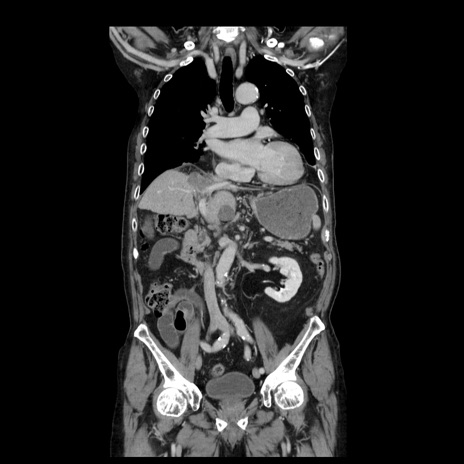

症例21(冠状断像)

【症例】70歳代男性

【主訴】腹痛

【現病歴】肝硬変・肝細胞癌にてかかりつけの方。約9時間前に食後より腹痛出現。症状が徐々に増悪し、嘔吐出現したため来院。

【既往歴】肝硬変、肝細胞癌(RFA、TACE後)

【身体所見】意識清明、表情苦悶様、BT 36℃、BP 129/78mmHg、P 88bpm、SpO2 97%(RA)、右上腹部から心窩部にかけて圧痛あり、反跳痛なし、筋性防御あり。

【データ】WBC 5800、CRP 0.16